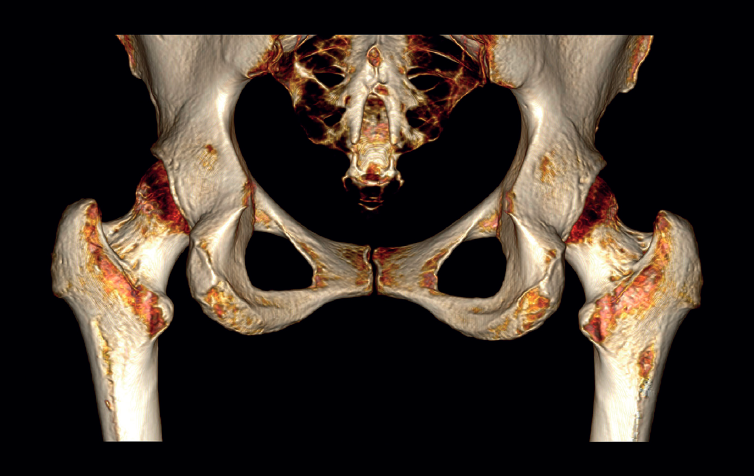

The physical examination revealed a limp-free gait and complete joint balance, with no positive signs of femoroacetabular impingement or inguinal pain. Muscle strength was preserved and similar to that of the contralateral side. She experienced intense pain on palpation of the insertion of the gluteus maximus, referred proximally to the ipsilateral buttock. The pain was reproduced on extension against resistance, and prevented sitting for long periods. Plain radiographic and computed tomography (CT) images revealed calcific tendinosis affecting the aponeurotic prolongation of the gluteus maximus in proximity to its insertion in the upper region of the linea aspera of the femur (Figures 1 and 2) Magnetic resonance imaging (MRI) of the hip showed a labral tear, that proved asymptomatic in the physical examination. In view of the clinical picture of radicular pain, an MRI scan of the lumbar spine and subgluteal space was also performed, ruling out radicular involvement or sciatic neuritis. Her previous treatment over the three years of evolution of the disorder included oral nonsteroidal anti-inflammatory drugs, a specific physiotherapy programme and several ultrasound-guided corticosteroid injections with positive results - though a last session showed no response. Due to the severity and chronicity of the symptoms and their resistance to conservative treatment, surgery was decided to clean and remove the intratendon calcification endoscopically.

In cases of calcific tendinopathy of the gluteus maximus, calcifications in the femoral metaphysis can be seen on plain radiographs, though a normal image may also be seen. Therefore, CT and/or MRI scans are usually necessary for establishing the diagnosis, exhibiting an irregularity or cortical erosion at the insertion of the gluteus maximus in the gluteal tuberosity, located on the posterolateral surface of the femur, distal to the greater trochanter, accompanied by areas of tendon calcification, local inflammatory signs and, in some cases, partial intratendinous ruptures(17). Use can also be made of CT-guided single-photon emission computed tomography (SPECT-CT), which pinpoints the anatomical location and assesses the activity of the lesion, and is of interest in the differential diagnosis in oncological patients(18).